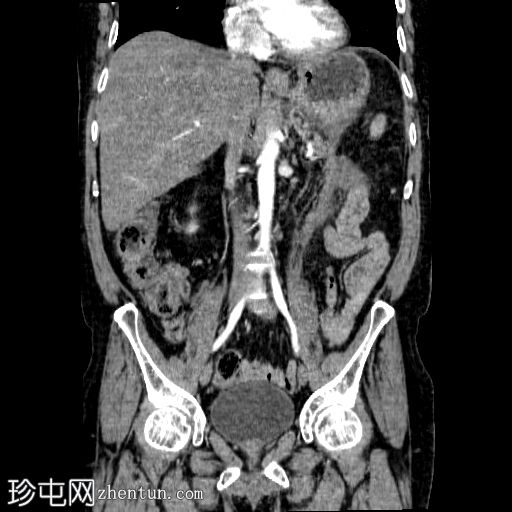

冠状C+动脉期

胰体尾弥漫性增大,特征为胰腺实质低强化,无明显坏死区域。

该病灶与以下表现相关:

胰周筋膜平面边界不清的污迹,无明显壁形成、气室、固体碎片或血液产物。

多个亚厘米大小、非特异性的腹主动脉旁淋巴结和肠系膜淋巴结,可能具有反应性。

病变范围如下:

病变横向延伸至左前肾旁间隙,伴有Gerota筋膜增厚。

病变向下延伸至盆腔。

无肠系膜或脾脏血管阻塞的证据。

未见导管扩张或钙化。